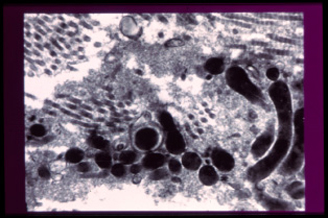

Aquí les dejo las maravillosas fotos de Microscopía Electrónica de Transmisión tomadas en el Conicet, premiadas en el Congreso Iberopanamericano de Periodoncia, en Agosto del 2001, representan las diferencias entre salud y enfermedad de células y bacterias dentro de la encía; y el póster al mejor trabajo premiado en el 2010 en la Asociación Latinoamericana de Osteointegración ALAO.

Bacterias que viven debajo de la encía y dentro de las células

ENFERMEDAD

Bacterias que viven debajo de la encía